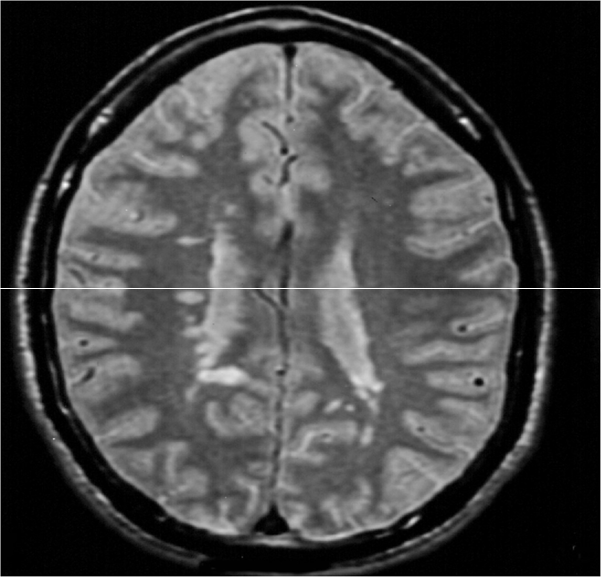

• MRI:

• This is particularly useful in detecting clinically silent lesions.

• More than 90% of patients with clinically definite MS have abnormal MRI.

Brain MRI

Spinal Cord MRI